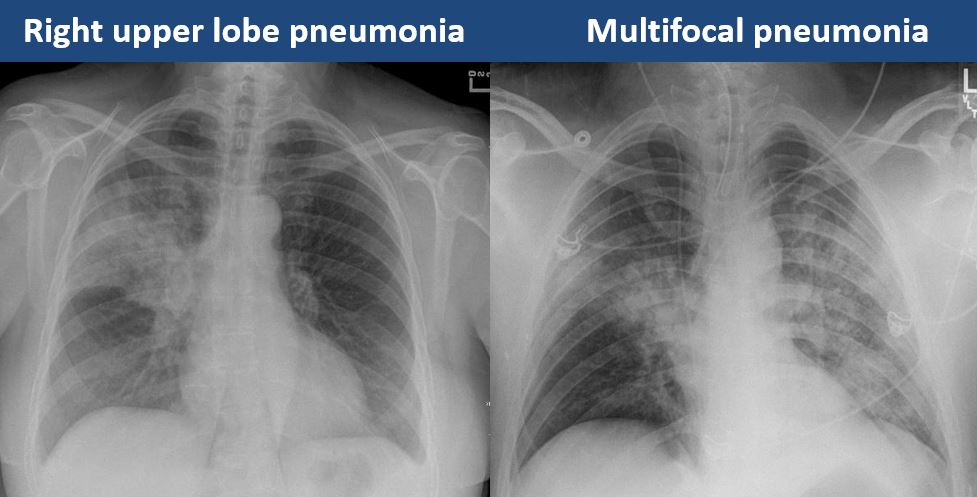

There is focal, multifocal, or diffuse airspace disease. [Yes/No]